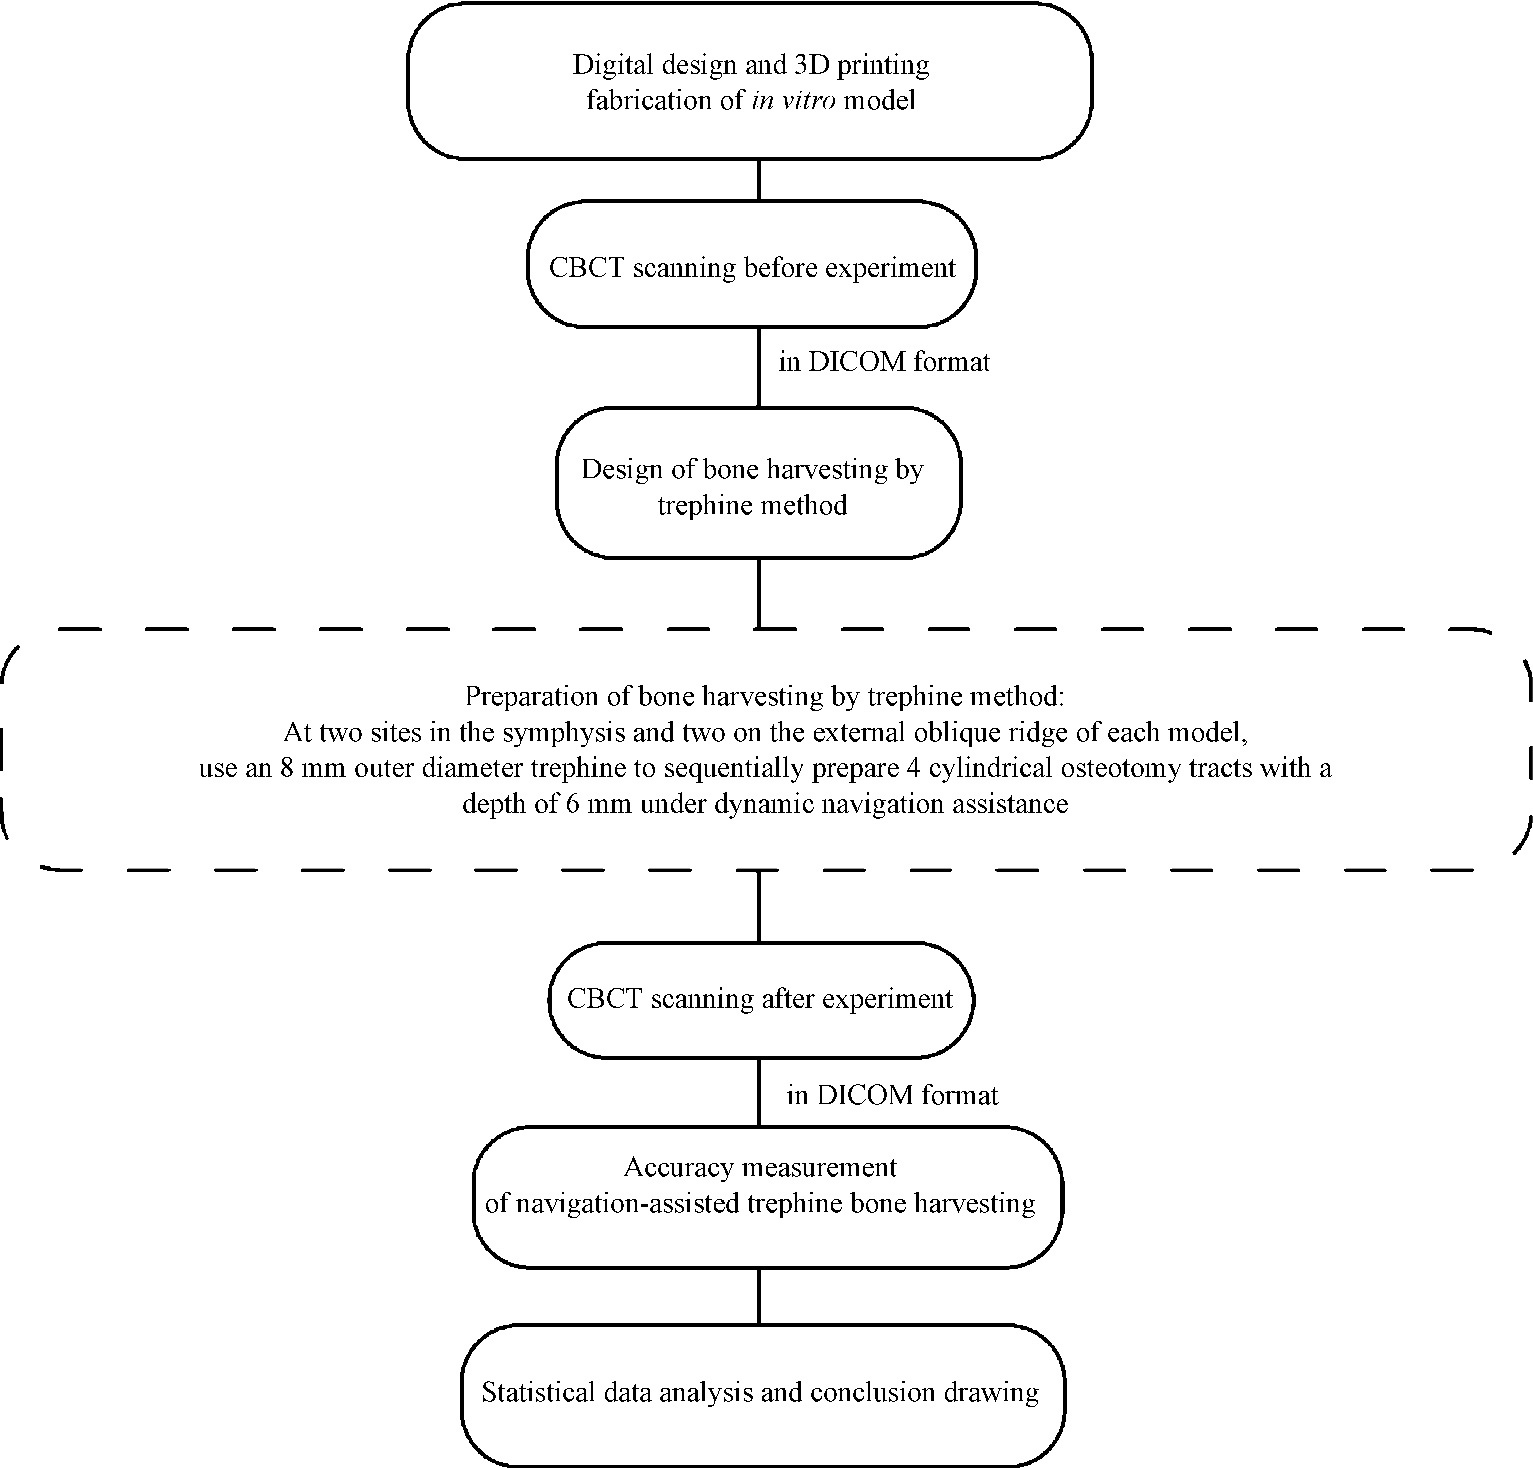

Accuracy of dynamic navigation-assisted trephine method for bone harvesting

Jiayu LIU, Ning ZHU, Yuchen CHANG, Xianming GAO, Yu ZHANG*( )

- Department of Oral Implantology, Peking University School and Hospital of Stomatology & National Center for Stomatology & National Clinical Research Center for Oral Diseases & National Engineering Research Center of Oral Biomaterials and Digital Medical Devices & Beijing Key Laboratory of Digital Stomatology, Beijing 100081, China